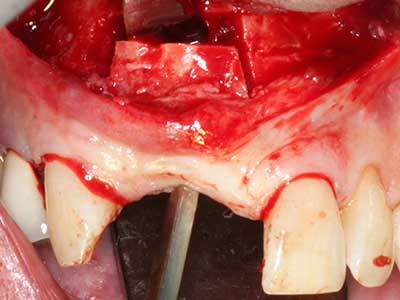

Bei der Knochenblockentnahme zeigen sich weitere Vorteile für die Piezochirurgie: Neben der bereits beschriebenen hohen Präzision bei der Osteotomie stellt sich gerade die Verwendung der dünnen Sägespitzen als besonders materialschonend heraus. Bei der Verwendung insbesondere von Lindemannfräsen sind mit deutlich höheren Entnahmeverlusten durch die dickere Instrumentenspitze zu rechnen (Lakshmiganthan, Gokulanathan et al. 2012). Die insbesondere bei retromolar entnommenen Blocktransplantaten notwendige basale Abtrennung wird durch speziell hierfür vorgesehene rechtwinklige Sägen erleichtert, so dass die Piezochirurgie als präzises, übersichtliches und sicheres Verfahren zur retromolaren Knochenblockgewinnung angesehen wird (Happe 2007) (Abb. 1-12).